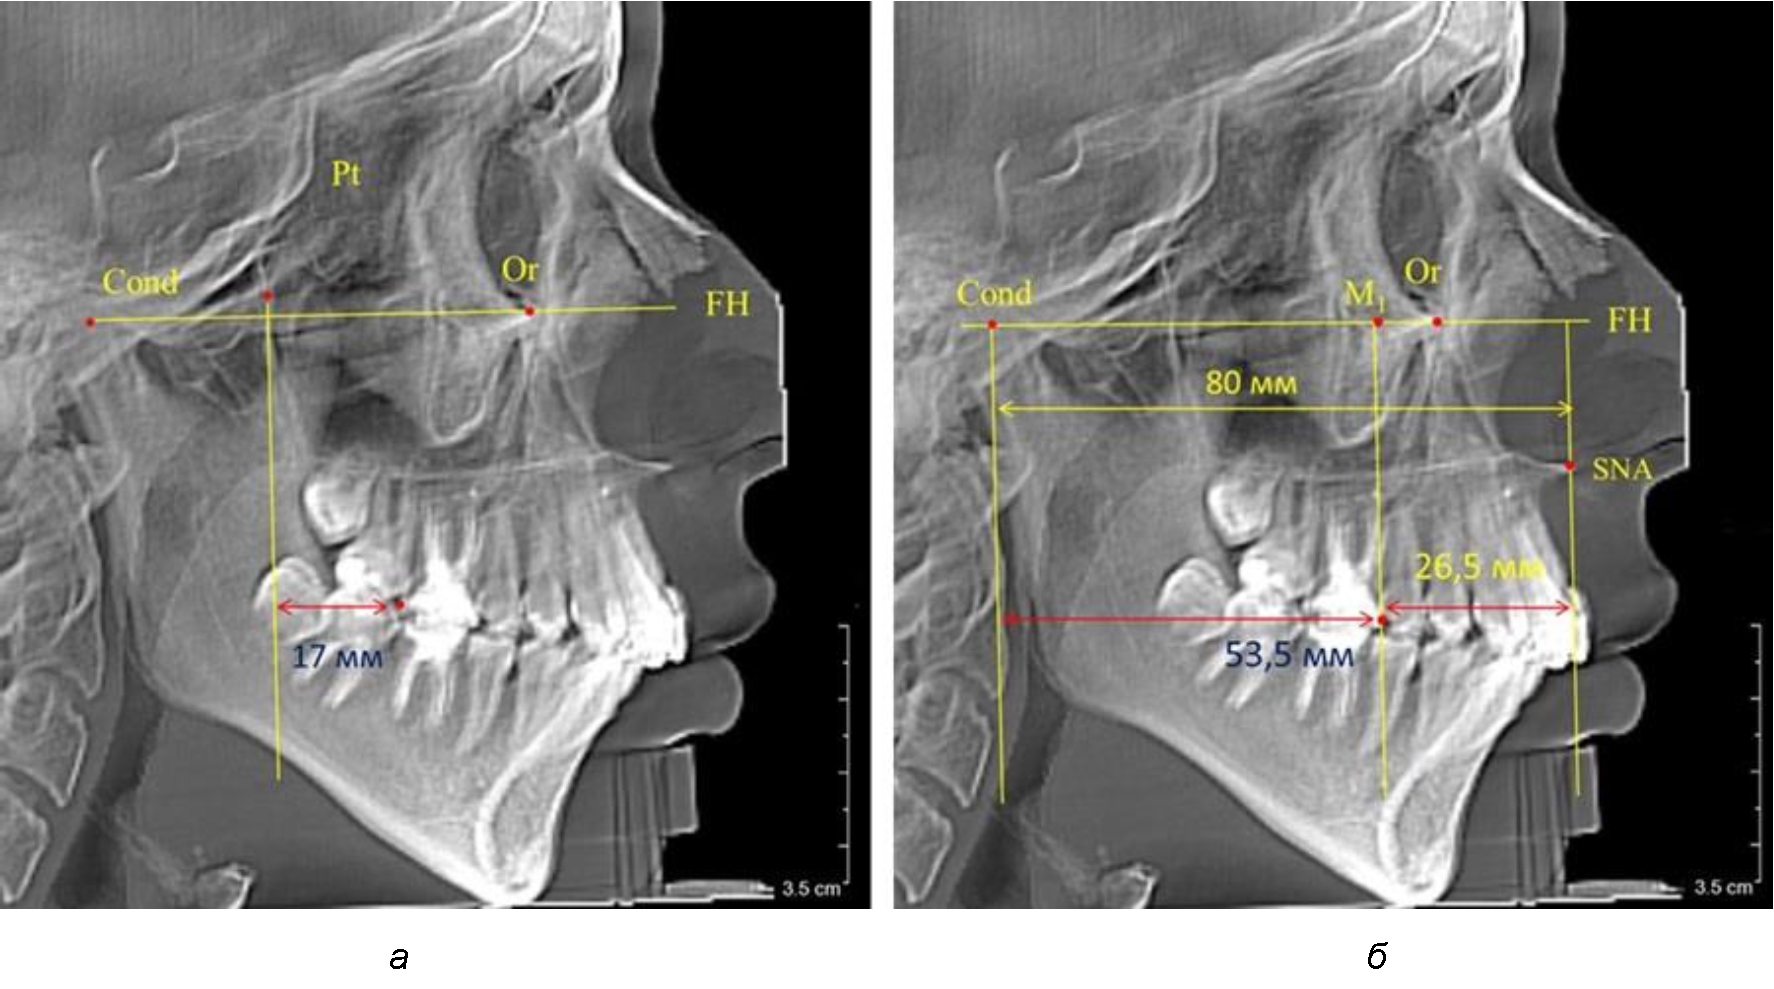

В то же время при увеличенном расстоянии от крыловидной вертикальной плоскости PTV до дистальной поверхности верхнего первого постоянного моляра, равное 23 мм, сагиттальный размер гнатического отдела составил 92 мм. При этом отношение кондилярно-спинального расстояния к кондилярно-молярному размеру (30,5), так же, как и при малых размерах, было близким к коэффициенту 1,5, что представлено на рис. 3.

Рис. 3. Особенности положения первых моляров по R. E. McDonald (а) и по предложенному методу (б) при увеличенном молярно-крыловидном расстоянии